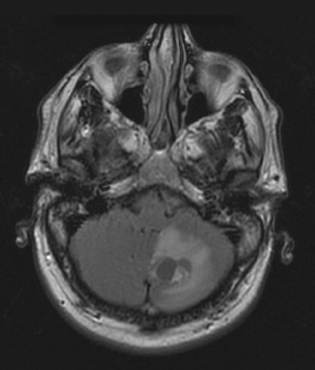

von hippel-lindau syndrome

Joseph F. DeMario, DO

<p class="p1"><img src="/sites/default/files/images/1209Con_PCVHLSynd.jpg" alt="Von Hippel-Lindau Syndrome " title="Von Hippel-Lindau Syndrome "...